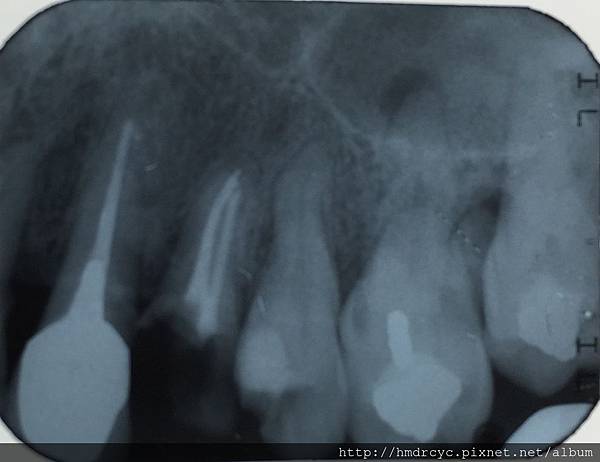

在X光上面是這樣的

X光一般病友不容易看懂

高雄欣美欣樂牙醫標示一下

這顆牙齒我們一樣治療到根尖化膿的位置

牙齒內的狀況只能從X光來確認